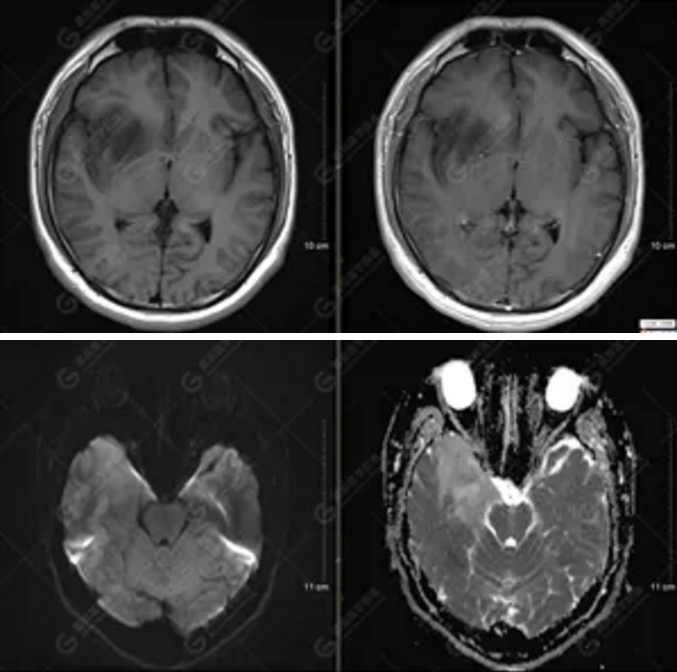

【MRI平掃及增強檢查所見】右側(cè)額顳島葉、右側(cè)海馬及右側(cè)基底節(jié)區(qū)見一團(tuán)塊狀異常信號影,累及右側(cè)下丘腦及視交叉,大小約5.1cm×4.5cm×4.3cm,呈長T1長T2信號,F(xiàn)LAIR序列呈等、稍高信號,DWI序列呈稍高信號,ADC圖高信號,增強后無明顯強化;病灶周圍見片狀長T1長T2水腫信號影,F(xiàn)LAIR序列呈高信號,病灶內(nèi)見右側(cè)大腦中動脈穿行。余腦實質(zhì)內(nèi)未見局灶性信號異常,增強后未見異常強化。右側(cè)側(cè)腦室輕度受壓,余腦室、腦池大小、形態(tài)均正常,中線結(jié)構(gòu)居中

圖1為多體素MRS檢查,感興趣區(qū)為正常腦組織的MRS表現(xiàn)。圖2為單體素MRS,右側(cè)顳葉病灶內(nèi)NAA峰明顯下降,Cho峰明顯升高,NAA/Cr值為0.1,Cho/Cr值為3.64。